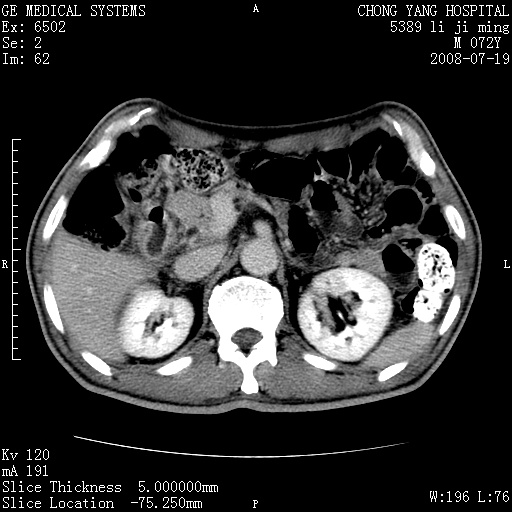

以下是引用zjzjr在2008-7-19 20:57:00的发言:[br]胰头增大,边缘模糊,周围可见渗出影,右侧肾前筋膜增厚.支持胰腺炎.

以下是引用yangyudong333在2008-7-20 6:56:00的发言:[br]胰腺增大尤以胰头明显,边缘模糊,周围可见渗出影,右侧肾前筋膜增厚,肠管於涨.支持胰腺炎

以下是引用不学无术在2008-7-19 23:15:00的发言:[br]胰腺增大尤以胰头明显,边缘模糊,周围可见渗出影,右侧肾前筋膜增厚,肠管於涨.支持胰腺炎